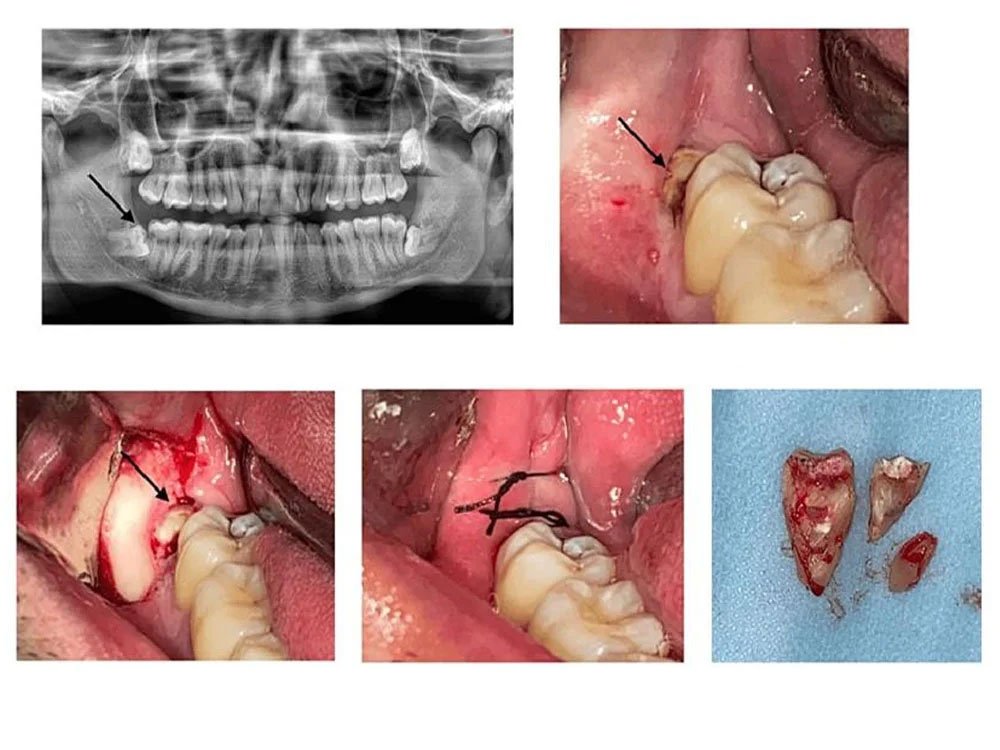

Impacted teeth are teeth that fail to erupt properly through the gum line. This most commonly occurs with third molars, also known as wisdom teeth, which often do not have enough space to emerge properly. Impacted teeth can remain fully or partially embedded in the gums or jawbone, which may lead to pain, swelling, infection, or damage to surrounding teeth.

If you experience any of these symptoms, our team can perform a clinical and radiographic evaluation to assess the condition and plan the best course of treatment.

At Dr. Radhika Multispecialty Clinic, we combine clinical expertise with compassionate care. Our skilled dental surgeons are trained to perform both simple and surgical extractions, including the removal of impacted wisdom teeth and complex root extractions. With our advanced diagnostic tools like digital X-rays and CBCT scans, we can identify the exact position of the tooth and plan the safest and most efficient extraction.